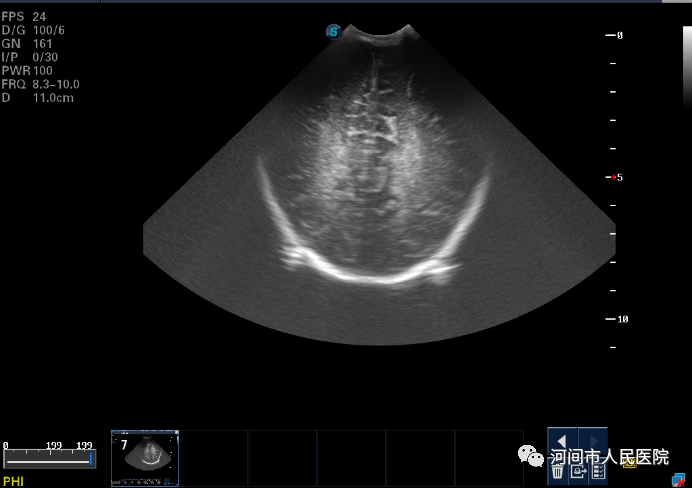

▲新生兒(er) 腦積水